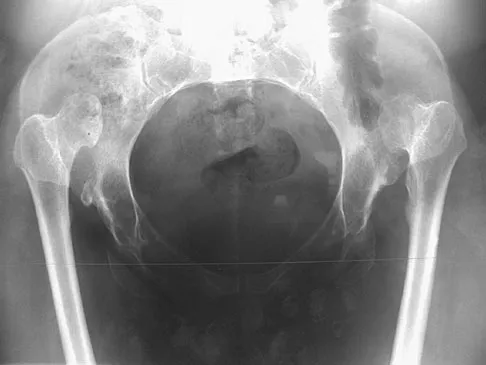

Question 50

An AP radiograph of the pelvis is shown in Figure 4. What muscle attaches to the avulsed fragment of bone identified by the arrow?

Question 52

A 22-year-old man has mild hip pain bilaterally and multiple skeletal lesions. Based on the pelvic radiograph shown in Figure 30, what is the inheritance pattern for his disorder?

A 68-year-old man reports a 4-week history of progressive left-sided lower back and hip pain. The pain is in the posterior buttock region with radiation to the groin and to the left anterior knee region. The pain is aggravated with walking and improves with rest. There is no history of previous trauma. Radiographs are seen in Figures 14a and 14b, and MRI scans are seen in Figures 14c through 14e. What is the most appropriate treatment option at this time?

Explanation